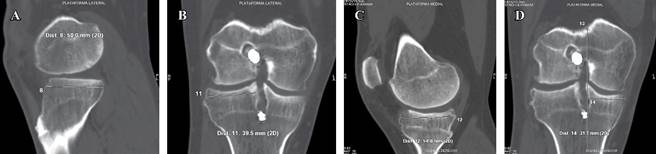

Con base en hallazgos radiológicos y características demográficas de nuestro paciente, existen pocas opciones terapéuticas que nos ayuden a evitar la progresión y osteoartritis del compartimento femorotibial lateral debido a antecedente de meniscectomía. Por todo lo mencionado, se decide que el trasplante meniscal en este caso en específico es una opción terapéutica válida y viable para evitar la progresión de la osteoartritis del compartimento femorotibial lateral. Para solicitar el aloinjerto de platillo tibial con menisco, se llevan a cabo mediciones radiológicas en tomografía computarizada de ambas plataformas tibiales de la rodilla derecha, la lateral (Figuras 3A-B) y la medial (Figuras 3C-D). Una vez hechas las medidas, se mandan al banco de aloinjertos y se lleva a cabo el «meniscus matching» para encontrar dentro de la disponibilidad del banco aquel aloinjerto con mayor compatibilidad y que más se asemeje morfológicamente al menisco nativo del paciente (Figura 4).

Figura 3: A) Tomografía computarizada de rodilla derecha en un corte sagital y B) coronal en las cuales se mide la plataforma tibial lateral en 50 mm en el plano AP y 39.5 mm en el plano laterolateral. C) Tomografía computarizada de rodilla derecha en un corte sagital y D) coronal en las que se mide la plataforma tibial medial en 54.8 mm en el plano AP y 31.7 mm en el plano laterolateral.